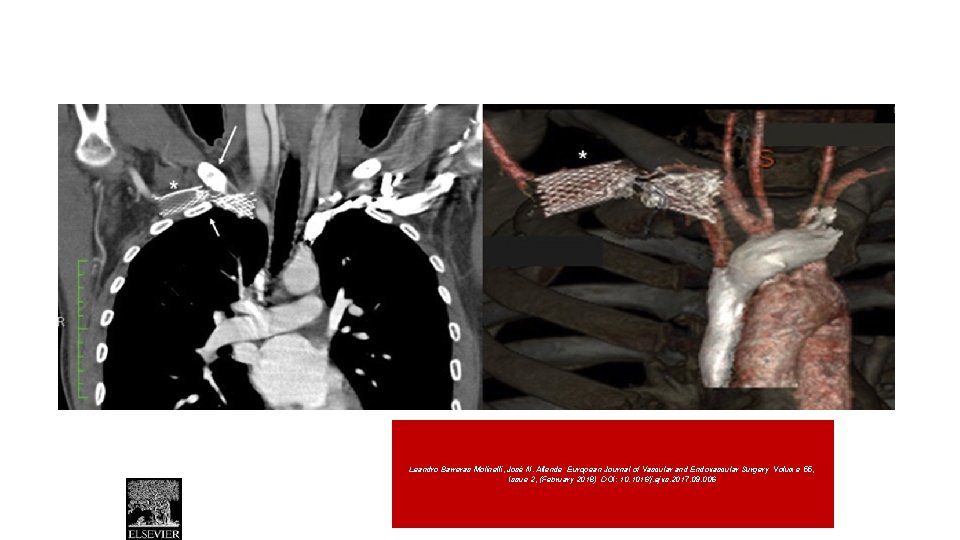

Paget-Schroetter syndrome therapy: failure of intravenous stents. • 22 patients had intravenous stents placed post-thrombolysis for Paget-Schroetter syndrome. All had post stent anticoagulation. In all patients the subclavian vein reoccluded 1 day to 6 weeks after stent insertion. Urschel HC et al, Ann Thorac Surg. 2003

• Primary subclavian vein stents are not recommended for venous thoracic outlet syndrome before surgical decompression by first rib resection due to a high risk of fracture because they are compressed between the clavicle and first rib.

Leandro Barreras Molinelli, José N. Allende European Journal of Vascular and Endovascular Surgery Volume 55, Issue 2, (February 2018) DOI: 10. 1016/j. ejvs. 2017. 09. 006 European Journal of Vascular and Endovascular Surgery 2018 55, DOI: (10. 1016/j. ejvs. 2017. 09. 006)